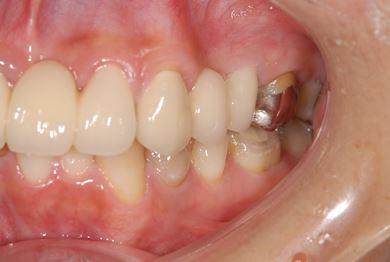

| 性別/年齢 | 女性 / 40歳 | ||||||||||||||||||||||||||||||||

| 主訴 | 前歯のさし歯の部分が目立ってしまい、新しくしたい。痛みも少しある。 | ||||||||||||||||||||||||||||||||

| 治療方針 | 保存不能な歯を抜歯し、セラミック治療にて、機能的・審美的回復を行う。 | ||||||||||||||||||||||||||||||||

| 治療内容 | ジルコニアフレームオールセラミッククラウン7本(オールセラミック用土台3本)、ハイブリッドセラミッククラウン1本、ハイブリッドセラミックインレー1本 | ||||||||||||||||||||||||||||||||